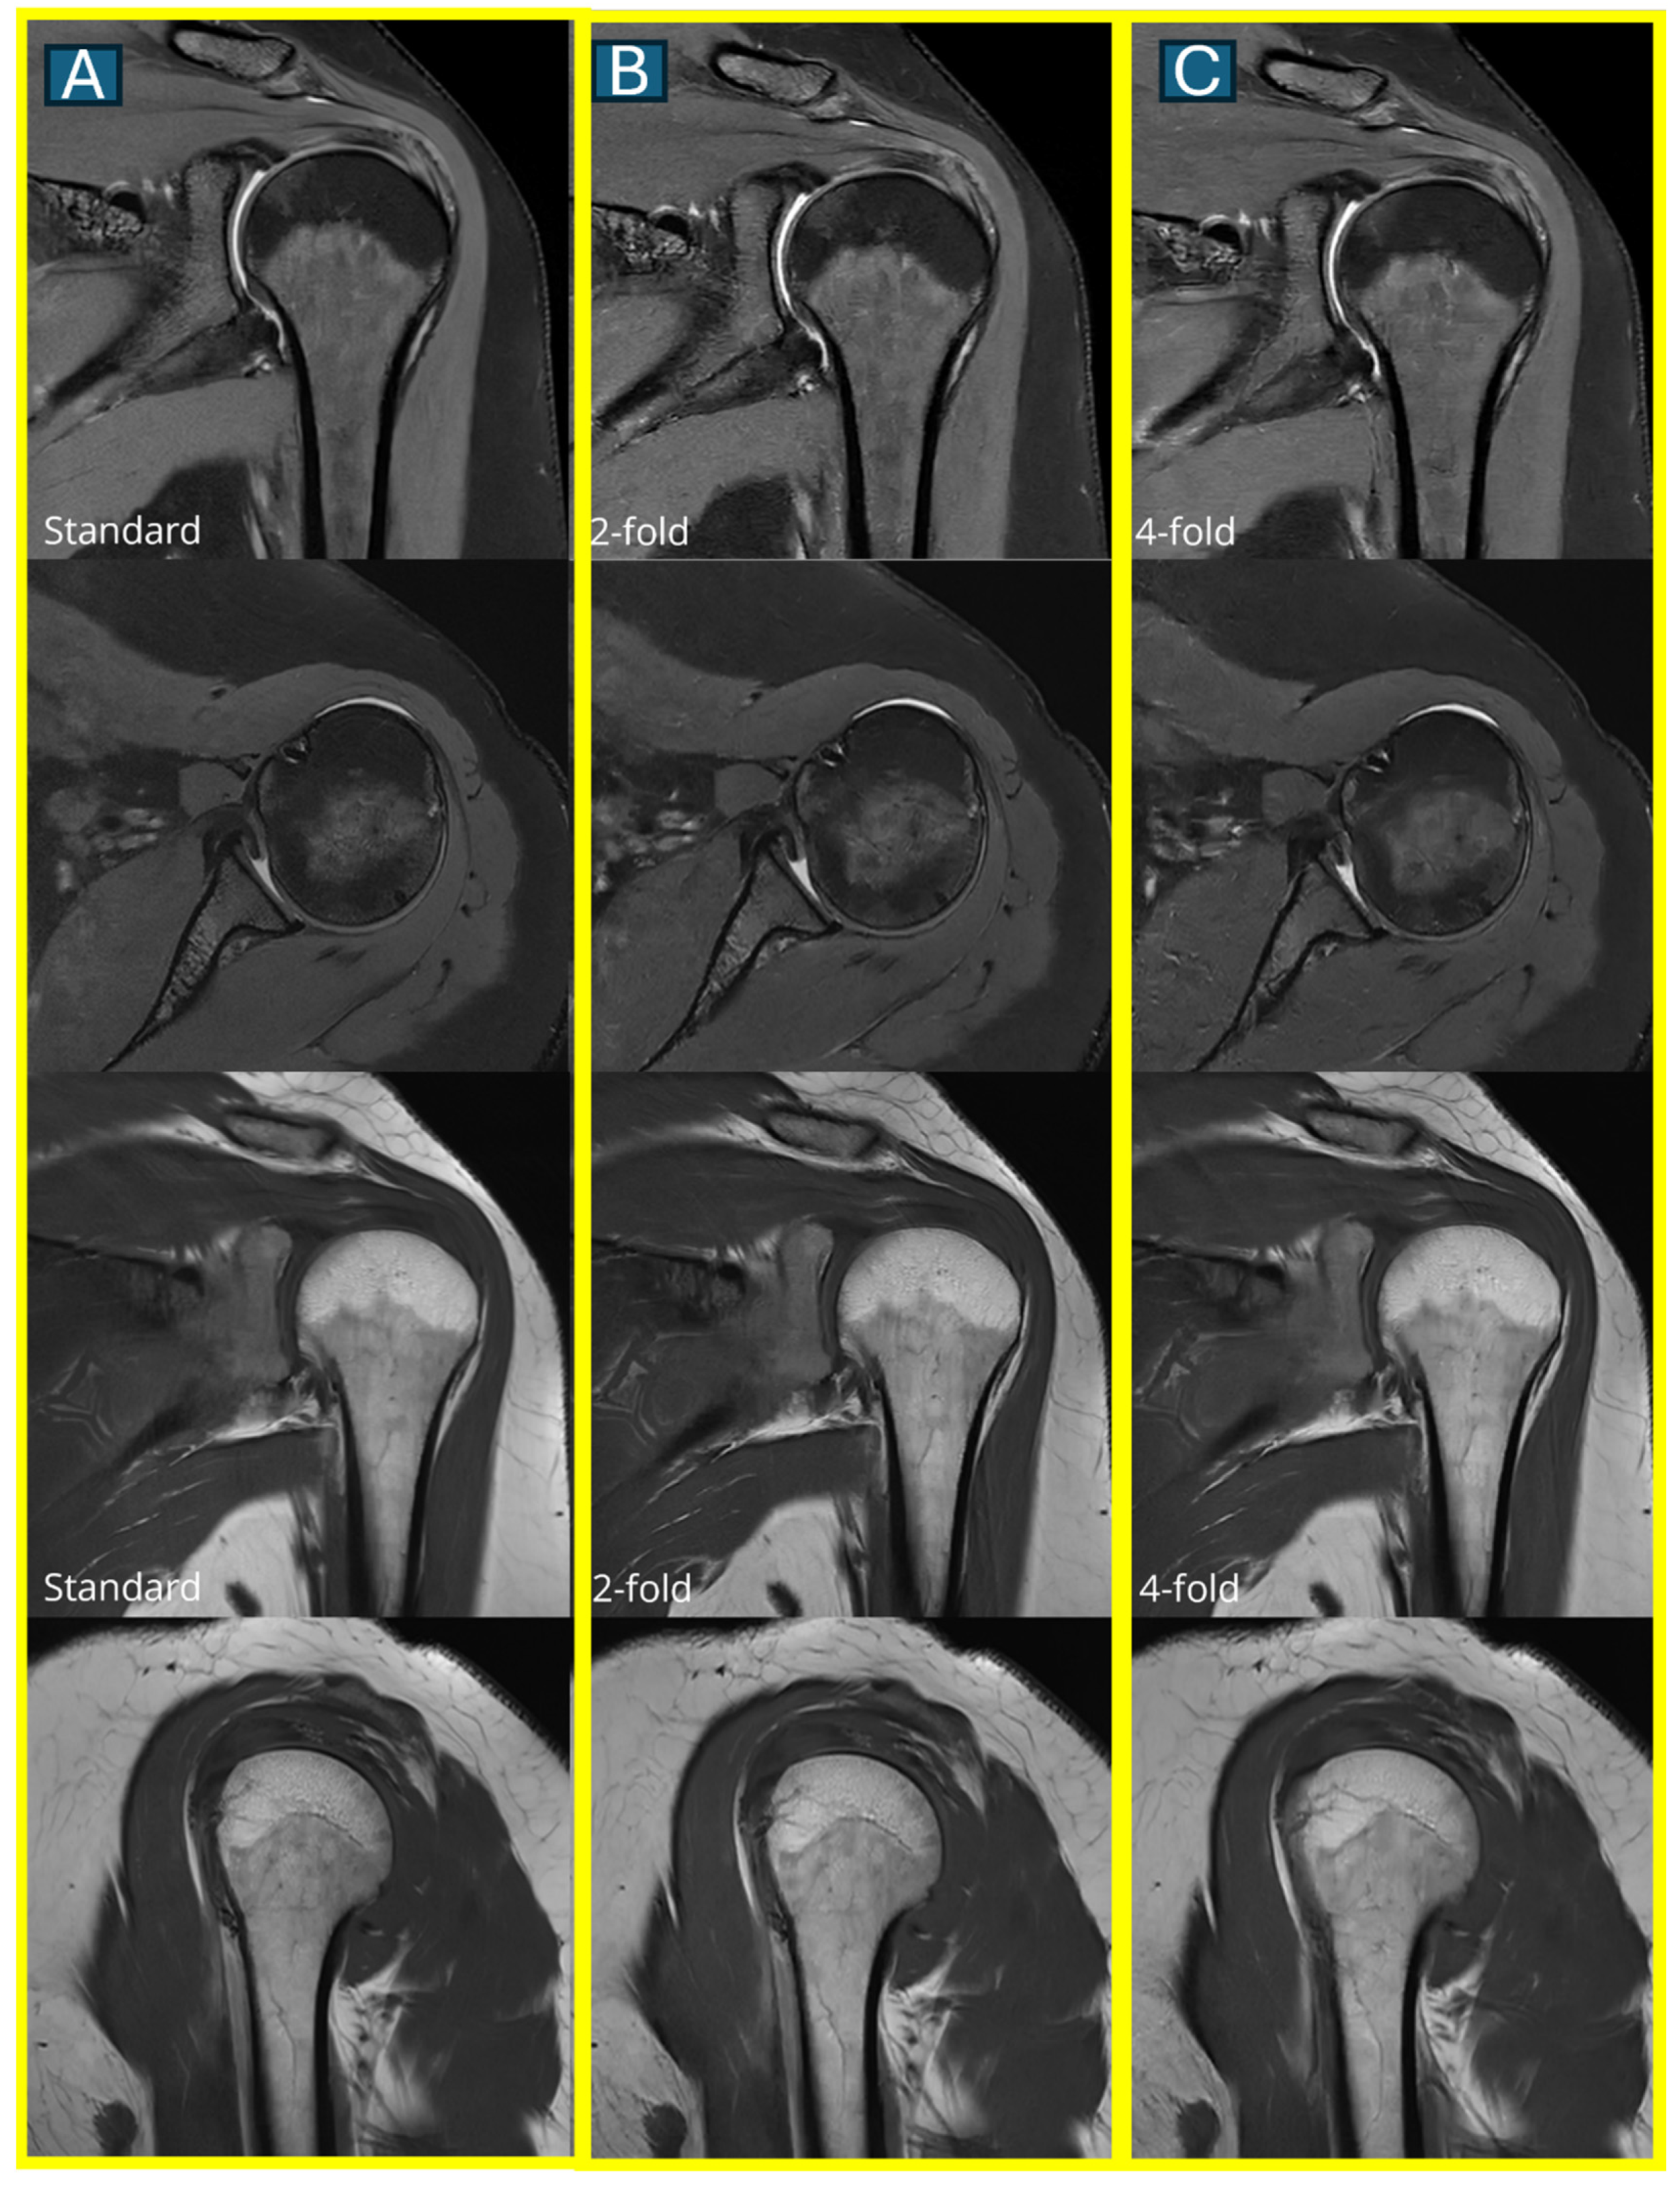

Figure 4. A comparison of image quality across all three protocols. Representative axial and coronal MRI images show a normal rotator cuff in a 45-year-old male. Images in the first column show the standard protocol (A), the second column shows the DL2 protocol (2-fold acceleration) (B), and the third column shows the DL4 protocol (4-fold acceleration) (C). Note the progressive subtle loss of fine detail with increasing acceleration, though all protocols maintain diagnostic quality.